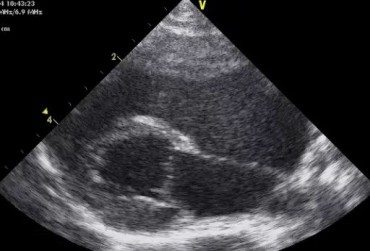

Badanie echokardiograficzne projekcja lewostronna koniuszkowa czterojamowa 2

19 lutego 2019

Urszula Bartoszuk